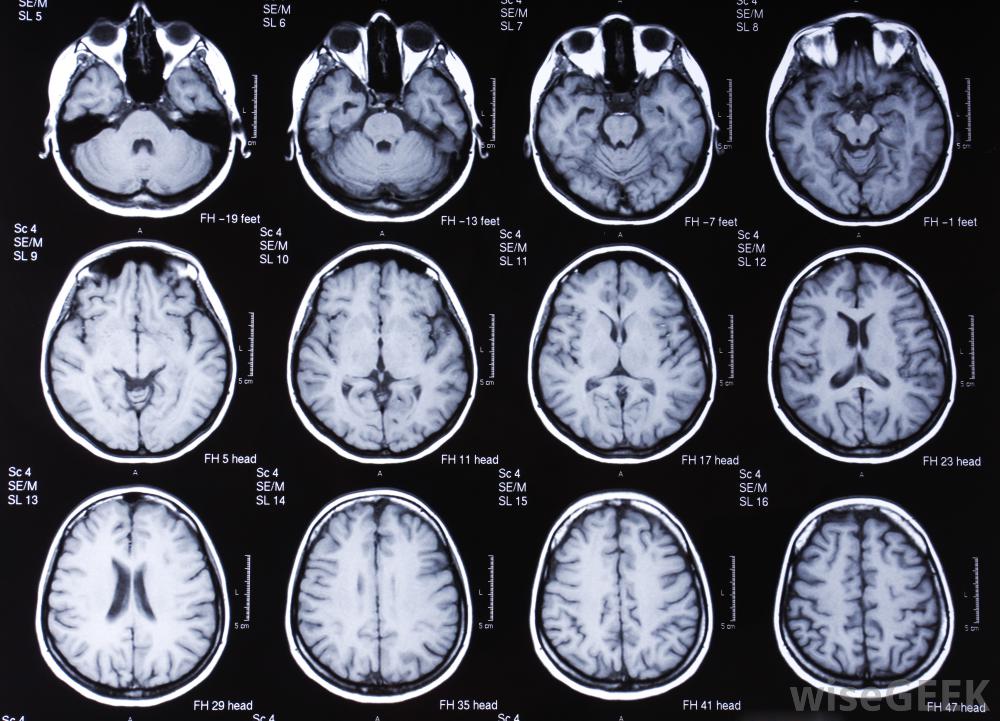

核磁共振成像和功能磁共振成像有什么區別(Differences between an MRI and fMRI)?

磁共振成像(MRI)提供身體內部結構的圖像,而功能磁共振成像(fMRI)則評估代謝過程。這兩種技術都能為醫療測試、隨訪和研究提供有價值的洞察患者體內發生的情況。MRI可用于身體的任何地方,雖然功能磁共振成像的研究集中在大腦,但成像能揭示活動水平的細微變化尤為重要。在某些情況下,患者可以同時接受核磁共振和功能磁共振成像掃描。腦部的核磁共振掃描。在核磁共振掃描中,其目標是獲得人體特定區域的解剖特征圖像,如腹部。該設備可用于生成高分辨率圖像,在這些圖像中,不同的器官將明顯不同于其他器官,并且腫瘤等異常情況很容易被發現。功能磁共振成像(fMRI)專門觀察大腦中的血液流動,并且檢測微小的變化。這使得測試能夠識別大腦的不同區域何時變得活躍,這可以幫助醫生或研究人員了解病人的大腦在做什么。核磁共振成像和功能磁共振成像通常是出于非常不同的原因核磁共振成像機利用磁共振成像技術來產生內部器官的圖像核磁共振成像和功能磁共振成像的一個關鍵區別是,核磁共振成像可以生成靜態圖像,這些圖像可以在以后查看病人身體內部的信息。在功能磁共振成像研究中,結果是大腦活動的實時記錄。它可以被凍結在各個幀上,比如大腦活動的一個亮點,例如,研究人員可能想用功能磁共振成像(fMRI)來識別大腦中與特定反應有關的區域,而醫生可能會命令進行測試,以了解患者為什么不能執行某些認知任務核磁共振成像機。在進行核磁共振或功能磁共振成像之前,需要對患者進行篩查,以確保手術的安全性。患者不能佩戴金屬,需要提醒技術人員任何醫療或在他們的身體里植入電子設備。他們還需要靜靜地躺在一個可能受限的環境中,除非一個設施有一個開放的核磁共振機器,這可能需要鎮靜劑來保持病人的平靜。核磁共振成像和功能磁共振成像研究中使用的設備聲音很大,有些病人戴著護耳裝置,其中可能包括帶音樂的耳機他們放松了。醫學專業人員可以檢查核磁共振掃描,以確定是否有內傷或疾病跡象根據核磁共振成像和功能磁共振成像的目的,患者可能會在設備上花費不同的時間。他們應該在手術前得到一個估計,以幫助他們計劃。一些研究還要求使用對比材料來增加某些結構的可見度,在這種情況下,患者在成像前不久接受注射。一些造影劑會引起過敏反應,患者應確保技術人員了解任何過敏史。功能磁共振成像必須實時解釋,而核磁共振成像可以拍攝靜態圖像。